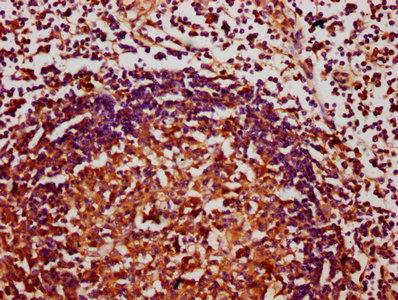

IHC image of CSB-PA618758LA01HU diluted at 1:400 and staining in paraffin-embedded human lymph node tissue performed on a Leica BondTM system. After dewaxing and hydration, antigen retrieval was mediated by high pressure in a citrate buffer (pH 6.0). Section was blocked with 10% normal goat serum 30min at RT. Then primary antibody (1% BSA) was incubated at 4°C overnight. The primary is detected by a biotinylated secondary antibody and visualized using an HRP conjugated SP system.